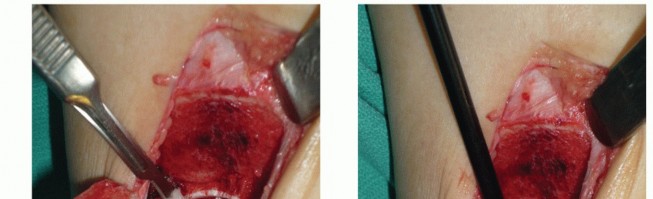

Closure

Medial closure

Reduction of the medial osteotomy after cartilage reconstruction

Temporarily place a drill bit in one of the predrilled holes to orient the reduction.

Confirm reduction by visualizing the anterior and posterior aspects of the osteotomy at the joint line.

We routinely use two partially threaded small fragment cancellous screws to fix the osteotomy under compression ( TECH FIG 7A,B ).

If fixation is suboptimal, two fully threaded cortical screws may be used to engage the opposite cortex. It may be necessary to use longer cortical screws from a pelvic set to reach the opposite cortex.

A buttress plate placed at the superior aspect of the osteotomy provides an antiglide effect ( TECH FIG 7C ). Confirm fluoroscopically that the osteotomy is anatomically reduced at the plafond.

A minimal gap will be present at the osteotomy site despite anatomic reduction due to the thickness of the saw blade.

Reapproximate the flexor retinaculum with the PTT in its anatomic position ( TECH FIG 7D ).

TECH FIG 7 • Reducing medial malleolar osteotomy. A. Reduced osteotomy is secured with two malleolar screws placed in the predrilled holes. B. View through arthrotomy confirms reduction of anterior tibial plafond. C. Medial buttress plate.

(continued)

Close the anterior arthrotomy (

TECH FIG 7E

).

The periosteum over the osteotomy may be reapproximated but must be coordinated with the antiglide plate.